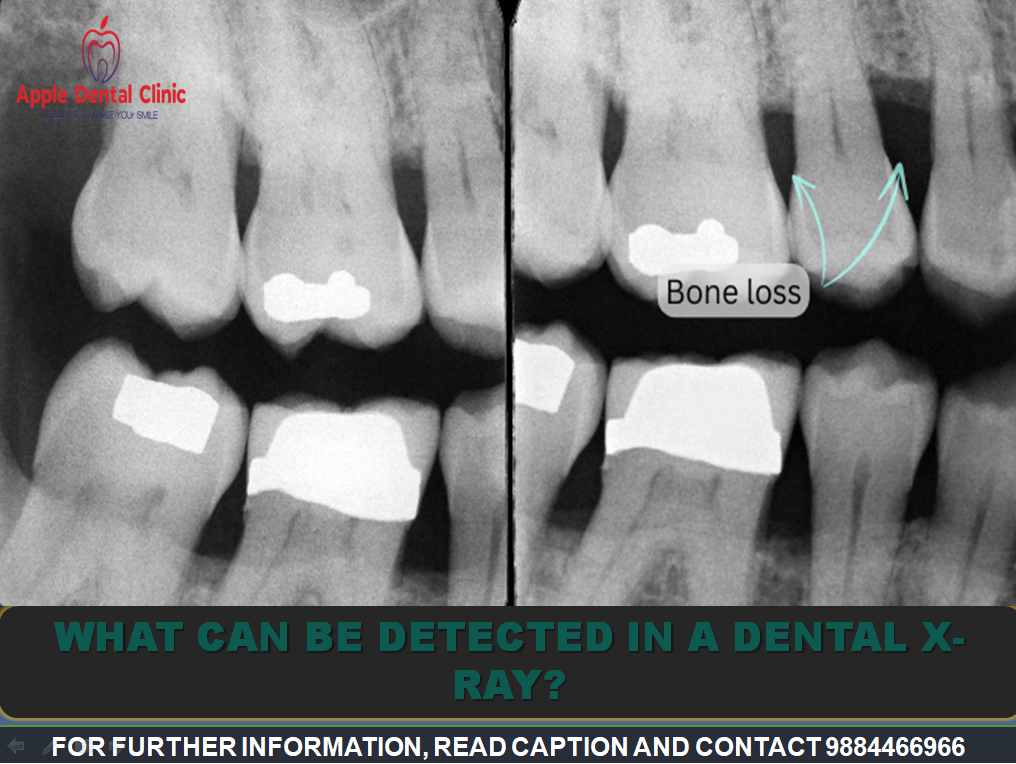

BEST ORAL CARE IN ANNA NAGAR! We use dental X-rays to detect or rule out a variety of oral health issues: Tooth decay – Areas of decay show up as dark spots in X-ray images. X-rays are especially helpful by revealing hard-to-see decay between teeth. Periodontal disease – Infection around the root of a tooth can occur below the gum line. Naturally, X-ray imaging must be used to see what’s going on. Cracks in teeth and fillings – Hairline cracks are often invisible to the naked eye, but become more obvious on X-ray. This is often an early sign that a crown will be needed to save the tooth. Cysts – Lumps, polyps, nodules and soft tissue growths below the gum line can be more readily seen with routine X-rays. Cancer – Bone and other types of cancers can be identified at an early stage, improving treatment options. Infection – X-rays can reveal certain bacterial infections. They become useful for detecting the possibility of a failed root canal. Bone loss – X-ray is an essential tool when diagnosing advanced cases of periodontal disease. Impacted teeth – X-rays can show the exact position of teeth that have not erupted yet. X-rays reveal their location and direction. Unerupted teeth – As children mature, X-rays confirm the position of permanent teeth. They also show any blockages to their proper eruption.